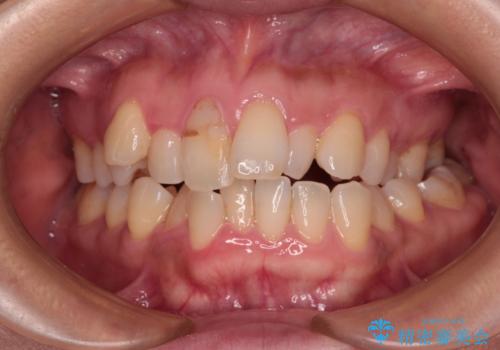

- 高校生の時に行った矯正治療の後戻りと、通院してもなかなか改善しない奥歯の痛みを気にして来院された患者様です。

まずは左下奥歯の根管治療を行い、痛みが引いたことを確認してから矯正治療を開始しました。

後戻りは軽微であったため、インビザライン・ライトにて歯列を整えました。